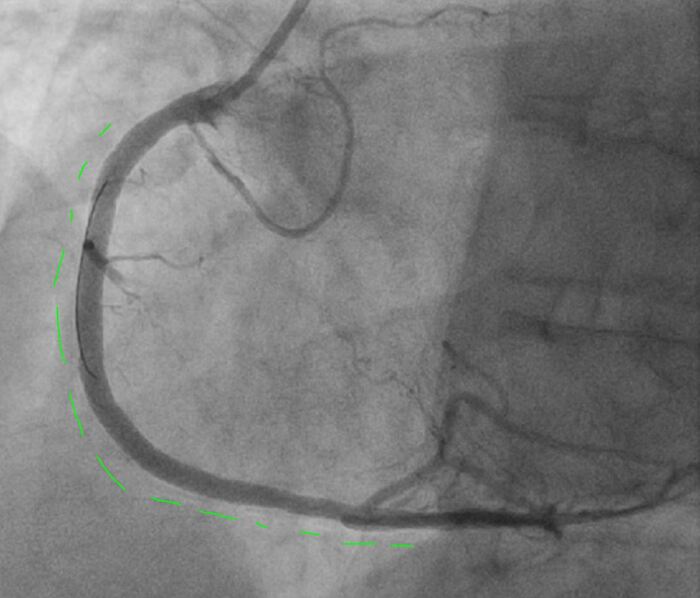

Левая коронарная артерия, проходима, без значимого поражения, дистальный кровоток свободен

Правая коронарная артерия, неровности контуров, кровоток свободный.

Контрастирование левого желудочка - дискинезия верхушки, передне-бокового и задне-диафрагмального сегментов, гиперкинез базальных отделов.